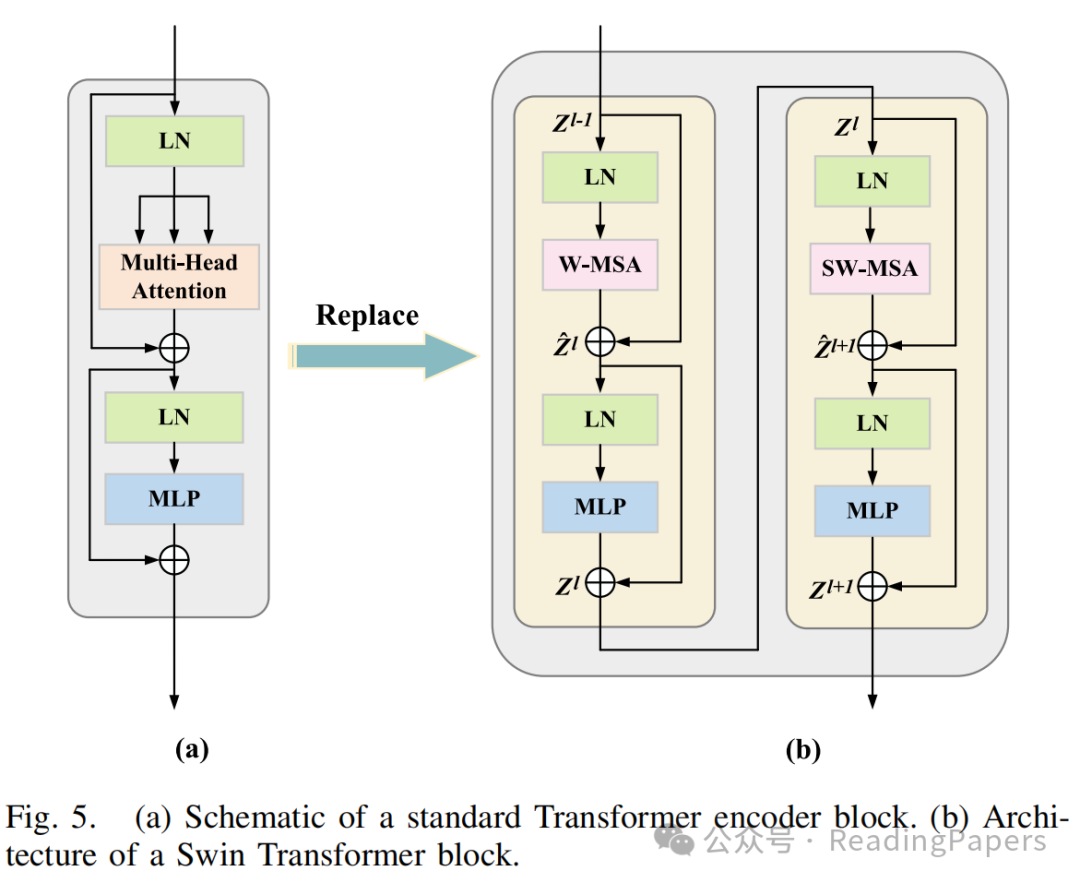

2) Swin Transformer模型

如图4所示,ViT对整个嵌入的图像块进行自注意力计算。典型的MSA模块中的一个主要问题是计算复杂度是图像空间维度的二次函数。Swin Transformer引入了W-MSA和SW-MSA技术来缓解这一限制。图5(b)显示了两个连续的Swin Transformer块,每个块由LayerNorm(LN)层、MSA模块、多层感知器(MLP)层和残差连接组成。此外,两个相邻的MSA块被替换为W-MSA和SW-MSA块。W-MSA的计算开销与图像大小呈线性关系,因为它在定义的窗口内进行自注意力计算。然而,由于这些窗口之间缺乏信息交换,其建模长距离依赖关系的能力有限。相比之下,SW-MSA引入了循环移位操作,将每个窗口向左上方向移动。这一策略使得各种不相邻的子窗口能够有效地相互交互。因此,Swin Transformer能够有效地建模上下文依赖关系并获取高效的分层特征表示。

在Swin Transformer中,输入特征图被划分为不重叠的窗口,每个窗口包含(本文中设置为7)个图像块。作为(S)W-MSA的输入,是一个长度为、维度为的图像块序列。基于这种窗口划分策略,Swin Transformer块的输入和输出可以表示为:

其中,和分别表示第个块的W-MSA和MLP的输出。类似地,和分别表示第个块的SW-MSA和MLP的结果。表示层归一化操作。根据先前的工作,自注意力计算如下:

其中,、和分别表示查询、键和值矩阵;表示查询或键的维度。、和表示三个投影矩阵的可学习参数。此外,表示偏置矩阵。